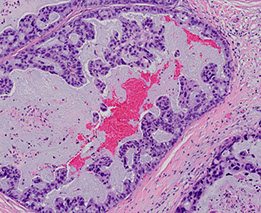

Mammary Analogue Secretory Carcinoma (MASC)

Tumor of the parotid c microcystic, papillary, and tubular patterns

- has a relation to acinic cell carcinoma and breast cancers, the genetics is mostly what makes it unique

- usually are slow growing lesions in the parotid of young males

- resembles secretory ca of the breast

IHC: (+) GCDFP-15, MUC1, BRST-2 and mammaglobin, CK, S100

- sometimes has (+) mucicarmine in intraluminal spaces

- negative HER2

Genetics: t(12;15)(p13;q25), ETV6-NTRK3 gene hybrid is diagnostic

MASC